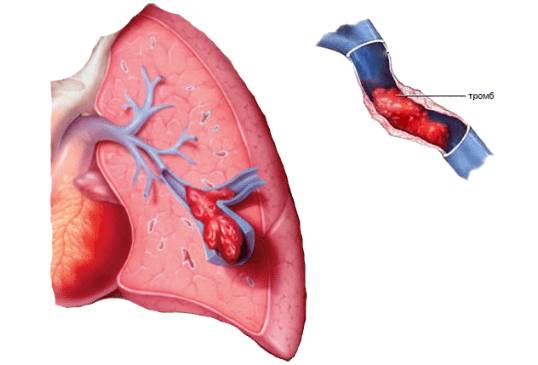

Ангиопульмонография

Это исследование с помощью рентгена, при котором в артерию вводят контрастное вещество. Нормально функционирующие артерии будут чётко видны, а закупоренные обрываются в местах «забитых» сосудов.